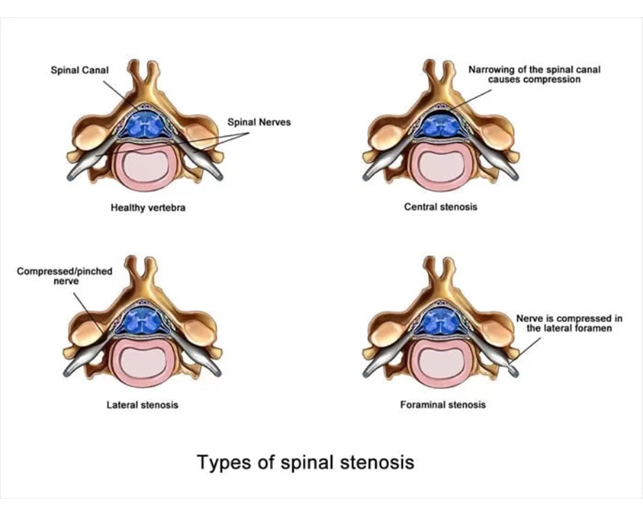

There are two important neural structures in the lumbar spine, dural sac and nerve root. The dural sac is a bag containing several nerve roots and lies in the center of spinal canal. A pair of nerve roots leave the dural sac at each level of lumbar spine and pass through lateral recess, foramen and extraforaminal area. The space should be adequate for the dural sac and nerve root to pass through, which if compromised start causing neurologic symptoms to the patient. This narrowing of the space for dural sac or nerve root is called spinal stenosis. The area stenosed determines the name of the stenosis like central canal stenosis, lateral recess stenosis or foramina stenosis. Central canal stenosis compresses the dural sac whereas lateral recess and foramina stenosis compresses the nerve root.

Central stenosis: Central stenosis may cause compression of central parts of thecal sac. It can be addressed by resection of the impinging bone of facet and hypertrophied ligamentum flavum using an ipsilateral full endoscopic interlaminar approach with additional extension of the procedure to the contralateral side (over the top technique)

Lateral recess stenosis: It causes compression of the traversing nerve root and lateral portions of thecal sac. This is best addressed by careful reaction of bone and ligamentum flavum through a full endoscopic interlaminar approach. A variety of burrs and Kerrison rongeurs are used to remove the impinging bone and soft tissue.